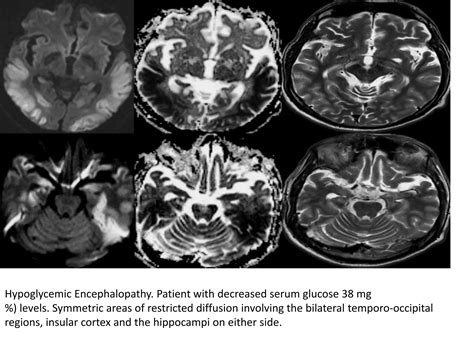

• toxic metabolic encephalopathy radiology